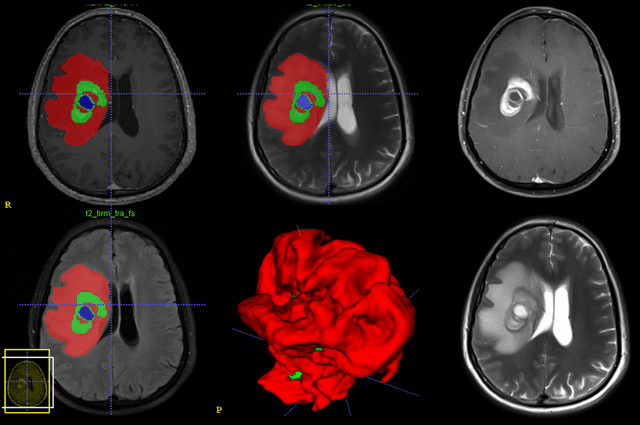

Purpose; The purpose of this study is to classify glial tumors into grade II, III and IV categories noninvasively by application of machine learning to multi-modal MRI features in comparison with volumetric analysis. Methods; We retrospectively studied 57 glioma patients with pre and postcontrast T1 weighted, T2 weighted, FLAIR images, and ADC maps acquired on a 3T MRI. The tumors were segmented into enhancing and nonenhancing portions, tumor necrosis, cyst and edema using semiautomated segmentation of ITK-SNAP open source tool. We measured total tumor volume, enhancing-nonenhancing tumor, edema, necrosis volume and the ratios to the total tumor volume. Training of a support vector machine (SVM) classifier and artificial neural network (ANN) was performed with labeled data designed to answer the question of interest. Specificity, sensitivity, and AUC of the predictions were computed by means of ROC analysis. Differences in continuous measures between groups were assessed by using Kruskall Wallis, with post hoc Dunn correction for multiple comparisons. Results; When we compared the volume ratios between groups, there was statistically significant difference between grade IV and grade II-III glial tumors. Edema and tumor necrosis volume ratios for grade IV glial tumors were higher than that of grade II and III. Volumetric ratio analysis could not distinguish grade II and III tumors successfully. However, SVM and ANN correctly classified each group with accuracies up to 98% and 96%. Conclusion; Application of machine learning methods to MRI features can be used to classify brain tumors noninvasively and more readily in clinical settings.